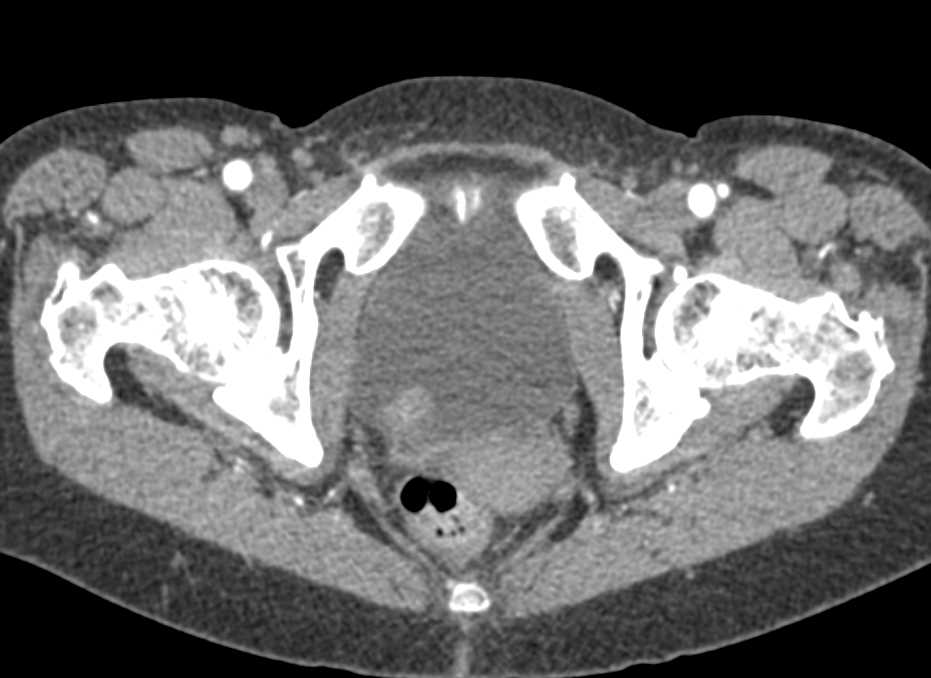

Obstructing Stone in the Left Ureter